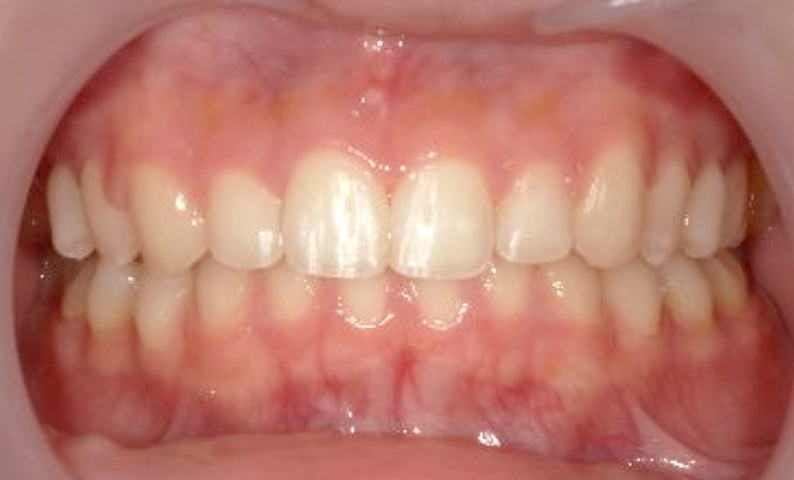

症例_002 上顎だけの部分矯正

治療期間:6ヶ月金額:24万円+税女性出っ歯上の前歯だけ

| Before | After |